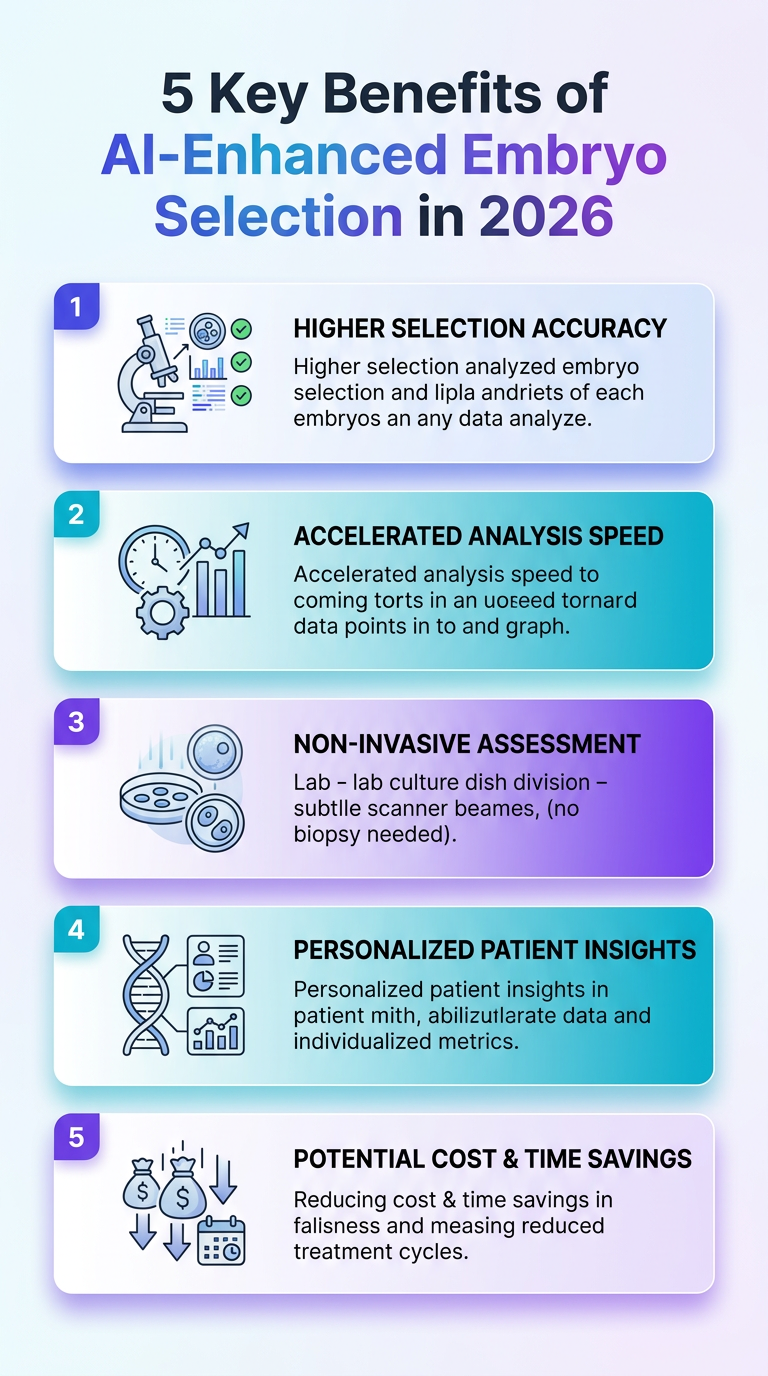

This infographic highlights five benefits of AI-enhanced embryo selection in 2026, including improved accuracy, faster decision-making, and data-driven ethics. A concise visual guide for readers exploring advances in reproductive technology.